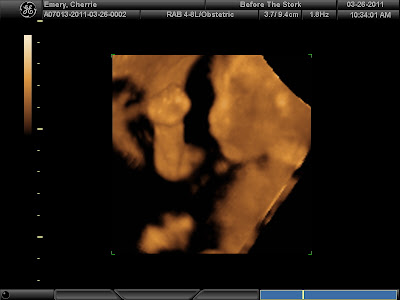

Straight on shot of her face...she's smiling here :)

This was pretty much what she did during the ultrasound...we are now calling her a boxer!

She must have felt my pain of my migraine...her head probably hurts too!

Boxing again...

Making a squishy funny face

Playing with her umblical cord...

Trying to hide her face from us...

She opened her mouth for us...

and of course stuck her tongue out!

She did a flip on us and showed us her beautiful spine...

good shot of her ear and her playing with the umblical cord...

everyone says she looks like neal...

her full body shot...

It was a really fun and great experience to have with our family. Their room was huge and had the most comfortable bed! Though it looked like she was boxing the whole time it was really fun to see her so active. The 4D was amazing cause you could even see the shadows and every movement of her tiny fingers. At one point during the video it looks like she's sign languaging to us. We got the Grow with Me package so we get to see her again in about 6-8 weeks...the lady said she'll be much chubbier and have more definite features...so it'll be exciting to compare how much she's grown!!!